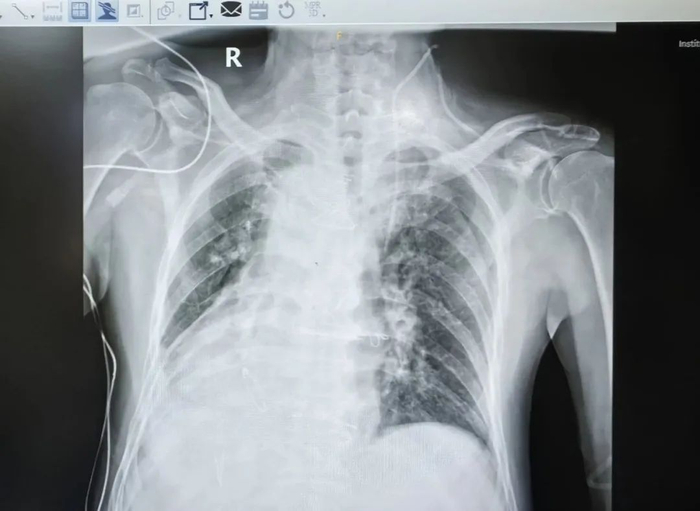

经检查发现,他是很罕见的“镜面人”。“镜面人”的心脏、肝脏、脾脏、胆等器官的位置与正常人相反,其中心脏位于右侧胸腔,心尖指向右下,又被叫做“镜面心”。

镜面人的出现几率仅为两万五千分之一,而在镜面心上实施修复手术的更是少见。

“因为患者的心脏位于右侧胸腔,术中主刀医生的站位、手术切口选择、缝合操作、甚至是手术器材等均要与常规手术相反,团队需要做好充分的术前准备,提前演练手术步骤。”尤庆生说道。